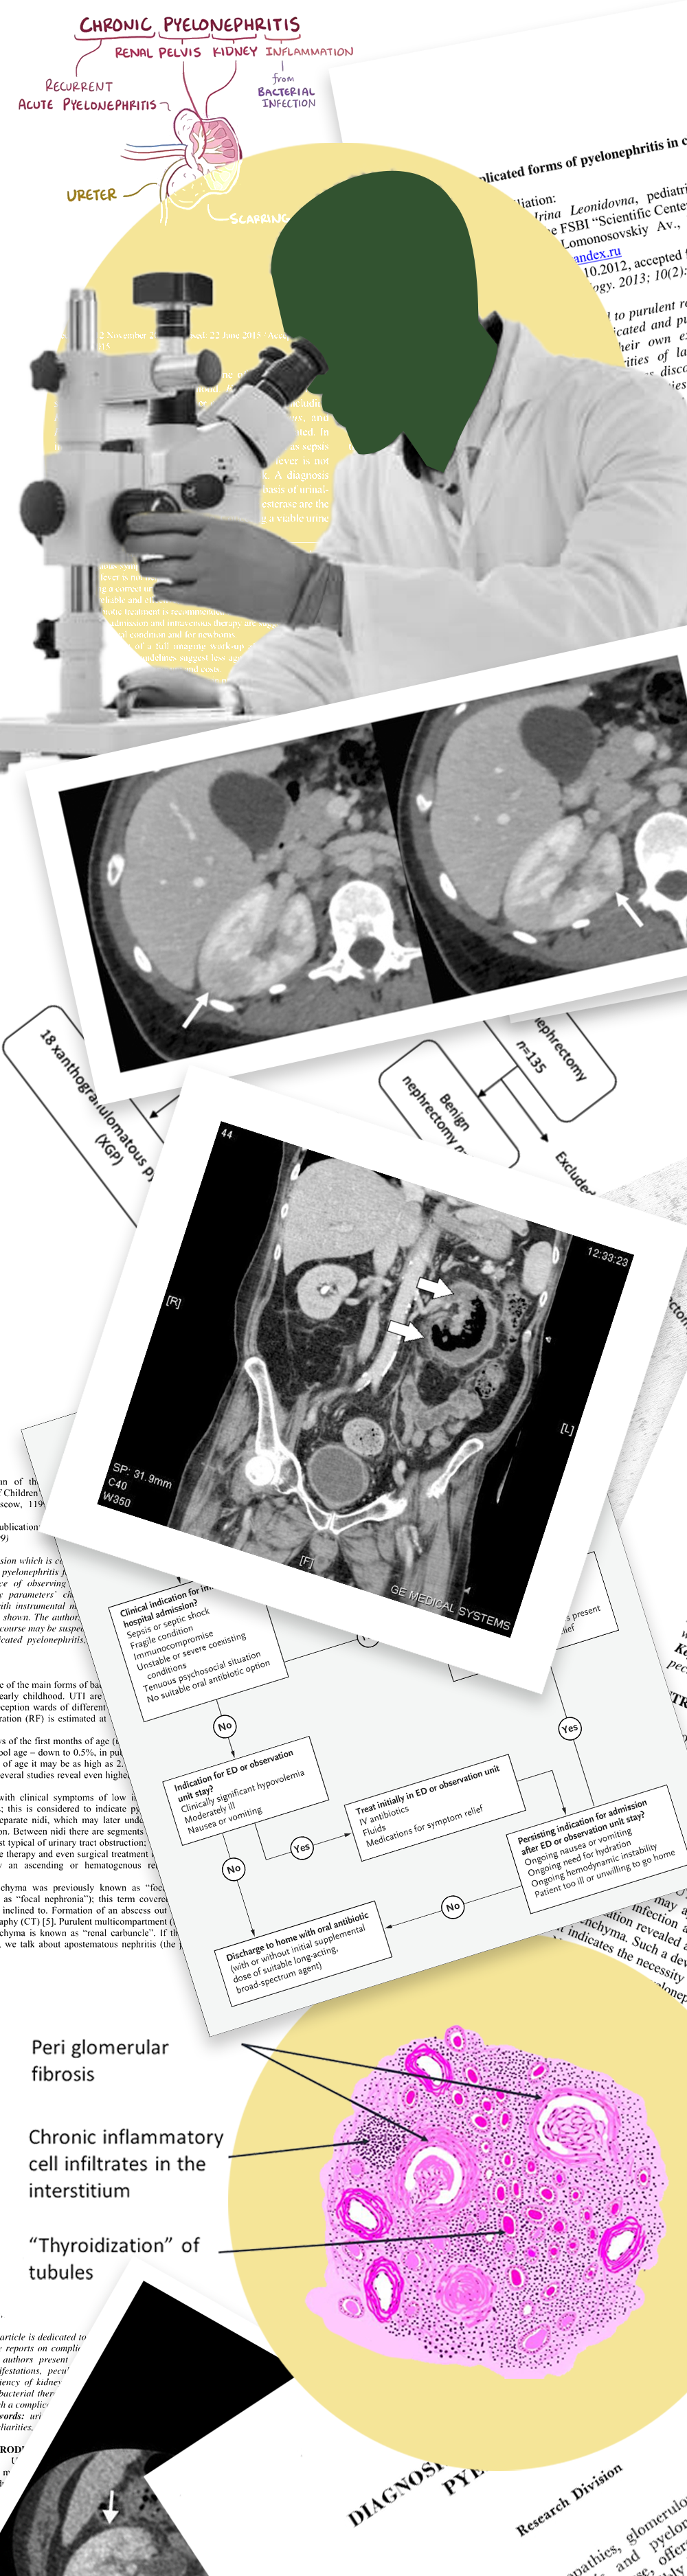

Pyelonephritis Diagnosis

To rule out kidney infections, the doctors may advise some of the following tests:

• Urine analysis to evaluate for blood, pus, and bacteria in the sample

• Urine culture to access the type of bacteria

Besides the above-mentioned tests, the doctor may also recommend the following tests:

• Ultrasound or CT - Performed to look out for a blockage in the urinary tract.

• Voiding cystourethrogram (VCUG) - A type of X-ray that looks for issues in the urethra and bladder. Doctors often perform these on children.

• Digital rectal exam (for men) - In this procedure, the doctor inserts a lubricated finger into the anus to check for a swollen prostate.

• Dimercaptosuccinic acid (DMSA) scintigraphy - This technique uses radioactive material to show kidney infection and damage.